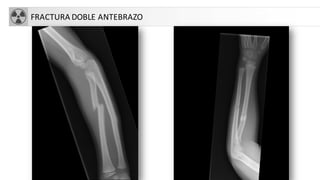

FRACTURASANTEBRAZO

• Se pueden presentar de forma conjunta (cúbito-radio)

• Fx Galeazzi: Fx diáfisis radial + Luxación radioulnar distal

• Monteggia: Fx cúbito (diafisaria)+Lux cabeza radio

• Complicaciones:

• Sd Volkmann

• Pseudoartrosis y consolidación defectuosa

• Artrosis

• Lesión N. mediano o cubital.

FRACTURA DOBLE ANTEBRAZO